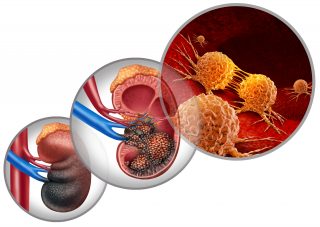

Urologic Cancers